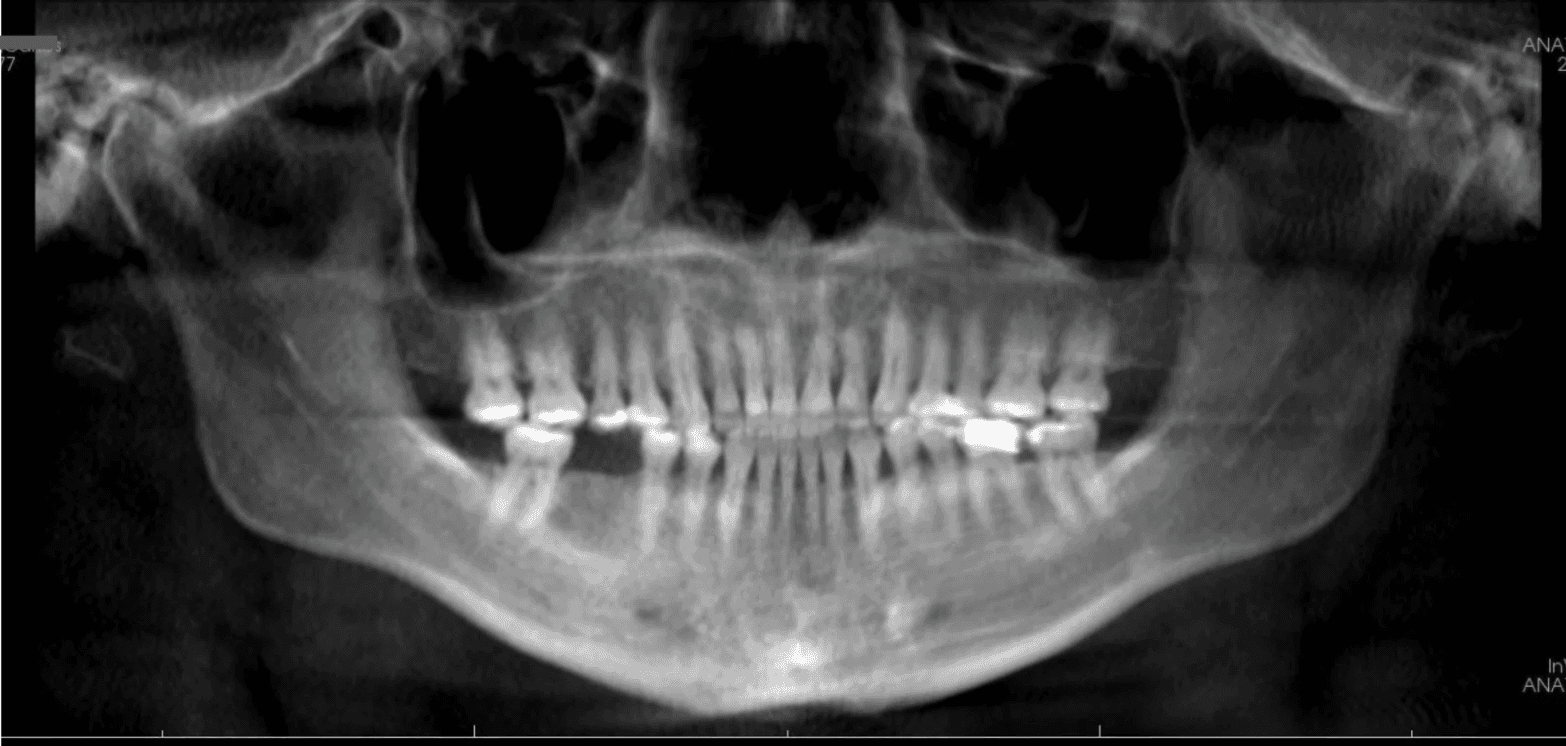

Final results

X-RAYS